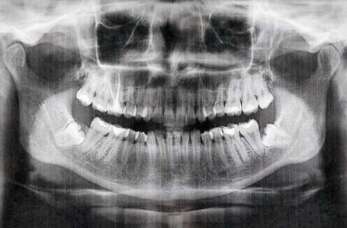

RTG zębów – komfortowe badanie w Dental Med

RTG zębów to istotny element diagnostyki stomatologicznej, jednak wiele osób obawia się tego badania. Strach często wynika z braku informacji na...